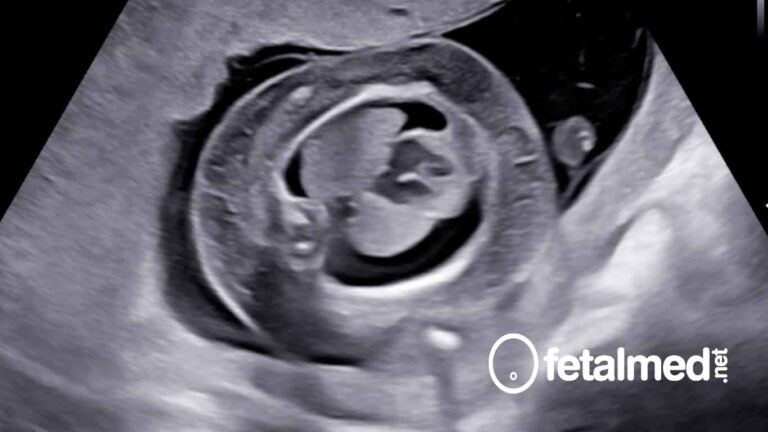

Hidropsia fetal: o que é e como tratar

Hidropsia fetal é uma condição grave onde o feto tem um acúmulo anormal de líquido em duas cavidades…

Escore cardiovascular na vigilância de fetos hidrópicos

A hidropsia fetal é uma doença grave do feto que está associada a uma alta mortalidade perinatal que…